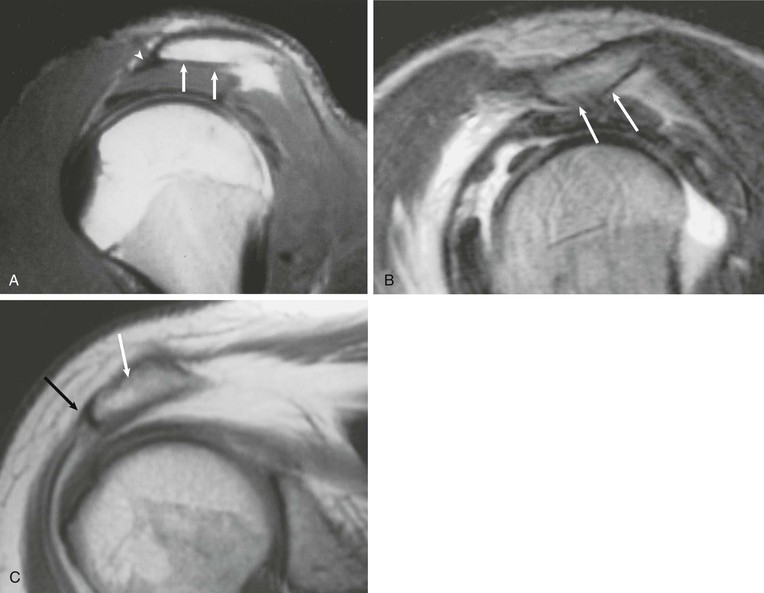

Partial-thickness tears (Figs. 44-18, 44-19, and 44-20) can occur on either the articular surface or the bursal surface or within the substance of the tendon. Articular surface tears are the most common type to occur (see Fig. 44-18). A partial-thickness tear is seen on MRI as an area of increased signal on T1-weighted images that increases to fluid signal intensity on T2-weighted images. The fluid signal intensity extends only partially through the thickness of the tendon from superior to inferior. These tears may partially heal with granulation tissue, making them difficult to distinguish from tendinopathy on MRI. MRA is more sensitive than conventional MRI in detecting articular surface tears; however, it does not increase sensitivity for detecting partial-thickness tears of the bursal surface. It has been suggested that the sensitivity for detecting partial-thickness undersurface tears can be further improved by adding the ABER view to the MRA protocol.55,104,105

Interstitial tears of the rotator cuff represent tears that occur within the substance of the tendon but do not involve the bursal or the articular surface (Fig. 44-19). These tears are demonstrated on MRI as a focal linear area of fluid signal that is contained within the substance of the tendon, and they typically occur at the footprint of the supraspinatus tendon as it attaches to the greater tuberosity of the humeral head.

A partial articular-sided supraspinatus tendon avulsion lesion is a subset of partial-thickness tears.106,107 The tear represents a partial-thickness articular-sided avulsion of the supraspinatus tendon at its most anterior attachment site. This type of tear deserves special attention and should be accurately described on MRI because the recommended treatment for this subset of tendon tears differs from the standard partial-thickness tears described previously. On MRI, a small articular-sided avulsion is seen as fluid signal extending into the articular surface of the supraspinatus tendon at its anterior attachment site with partial avulsion of the tendon at this level, and this lesion represents a subset of the articular surface partial-thickness tears (Fig. 44-20).

A full-thickness tear of the rotator cuff tendon is defined as a tear that extends through the complete thickness of the tendon from superior to inferior. This tear allows communication between the joint space and the subacromial-subdeltoid bursa. MRI criteria for establishing the diagnosis of a full-thickness tear include high (fluid) signal completely traversing the tendon from superior to inferior on T2-weighted images, a gap or absence of the tendon, and retraction of the musculotendinous junction (Fig. 44-21).

An intramuscular cyst within the rotator cuff (Fig. 44-27, A and B) has been described as a finding associated with small full-thickness tears or partial-thickness articular-sided tears of the rotator cuff.114 Intramuscular cysts are similar to paralabral cysts of the shoulder or meniscal cysts of the knee. Fluid leaks through a defect in the cuff and tracks in a delaminating fashion along the fibers of the tendon, resulting in a fluid collection contained within either the muscle or fascia of the rotator cuff. These cysts have been reported in the supraspinatus, infraspinatus, and subscapularis muscles and appear as oval lobulated collections of low signal intensity on T1-weighted images and high signal intensity on T2-weighted images. Identification of an intramuscular cyst of the rotator cuff should prompt a thorough search for a small associated cuff tear.